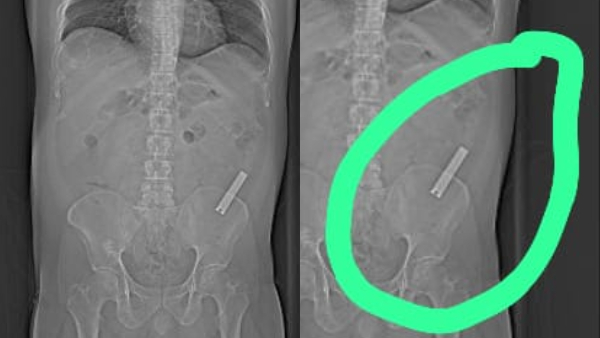

ಈ ವ್ಯಕ್ತಿ ನೈಲ್ ಕಟ್ಟರ್ ನುಂಗಿ 8 ವರ್ಷ ಆದರೂ ಕೂಡ ಆತನಿಗೆ ಆಗೆಲ್ಲ ಏನೂ ನೋವು ಕಾಣಿಸಿ ಕೊಳ್ಳುತ್ತಾ ಇರಲಿಲ್ಲ. ತೀರಾ ಇತ್ತೀಚೆಗೆ ಈತನಿಗೆ ಹೊಟ್ಟೆ ನೋವು ಕಾಣಿಸಿ ಕೊಳ್ಳುತ್ತದೆ, ಕೂಡಲೇ, ಆ ವ್ಯಕ್ತಿಯನ್ನು ಸ್ಥಳೀಯ ಆಸ್ಪತ್ರೆಗೆ ತೋರಿಸುತ್ತಾರೆ. ಆಗ ಸ್ಕ್ಯಾನಿಂಗ್ ಮಾಡೋದಕ್ಕೆ ಡಾಕ್ಟರ್ ಸಲಹೆ ಕೊಡುತ್ತಾರೆ.

ಬಳಿಕ ಈತನ ದೇಹದಲ್ಲಿ ನೈಲ್ ಕಟ್ಟರ್ ಇರೋದು ಗೊತ್ತಾಗುತ್ತೆ. ತಕ್ಷಣ ಆತನನ್ನು ಮಣಿಪಾಲ್ ಆಸ್ಪತ್ರೆಗೆ ದಾಖಲು ಮಾಡಲಾಗುತ್ತೆ. ಬಳಿಕ ವ್ಯಕ್ತಿಯ ಆರೋಗ್ಯ ಸ್ಥಿತಿ ಗಮನದಲ್ಲಿ ಇಟ್ಟುಕೊಂಡು ವೈದ್ಯರು ಆತನಿಗೆ ಶಸ್ತ್ರ ಚಿಕಿತ್ಸೆ ಮಾಡುತ್ತಾರೆ. ಆ ಚಿಕಿತ್ಸೆ ಯಶಸ್ವಿ ಆಗುತ್ತೆ, ಕೊನೆಗೆ ಈಗ ಆ ವ್ಯಕ್ತಿ ಡಿಸ್ಚಾರ್ಜ್ ಕೂಡ ಆಗಿ ಮನೆ ಸೇರಿದ್ದಾರೆ.

ಪಾನಮತ್ತನಾದ ವ್ಯಕ್ತಿ ನೈಲ್ ಕಟ್ಟರ್ ನುಂಗಿ ಸುಮಾರು 8 ವರ್ಷವೇ ಕಳೆದು ಹೋಗಿದೆ. ಆ ನೈಲ್ ಕಟ್ಟರ್ ಅನ್ನ ಮಣಿಪಾಲ್ ಆಸ್ಪತ್ರೆಯ ವೈದ್ಯರು ಈಗ ಹೊರ ತೆಗೆದು ಯಶಸ್ವಿ ಚಿಕಿತ್ಸೆ ನಡೆಸಿದ್ದಾರೆ. ಹೀಗಾಗಿ ವೈದ್ಯರ ಕೈ ಚಳಕದ ಬಗ್ಗೆ ಸದ್ಯ ಚರ್ಚೆ ಆಗುತ್ತಿದೆ. 8 ವರ್ಷಗಳಿಂದ ಹೊಟ್ಟೆಯಲ್ಲಿ ಇದ್ದ ನೈಲ್ ಕಟ್ಟರ್ ವೈದ್ಯರು ಹೇಗಪ್ಪಾ ತೆಗೆದರು ಅಂತ ಜನ ಬಾಯಿ ಮೇಲೆ ಬೆರಳಿಟ್ಟು ಯೋಚನೆ ಮಾಡುತ್ತಾ ಇದ್ದಾರೆ.